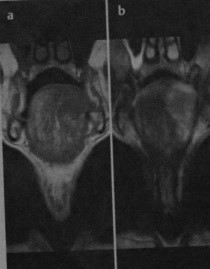

Рак языка. МРТ, П - взвешенное изображение без контрастирования (а) и последовательность с подавлением сигнала от жировой ткани (b) после введения гадолиния. При МРТ без контрастирования (а) выявляется плоскоклеточный рак, поражающий среднюю часть и переднюю треть тела языка с левой стороны. Опухоль имеет низкую интенсивность сигнала на Т1 -взвешенном изображении и не пересекает среднюю линию. После введения гадолиния (b) наблюдается интенсивное усиление опухоли. Исследование с контрастированием показывает истинное распространение опухоли, которая инфильтрирует альвеолярно-язычную борозду.